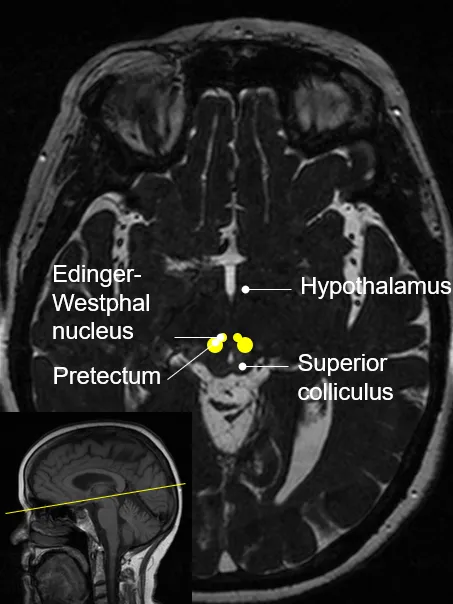

Anatomy (neuroanatomy) is a core & elective course in the Edinburgh Imaging Academy’s post-graduate MSc / Diploma programme portfolio. It can also be taken not-for-credit as CPD / CME & suitable for FRCR part 1 training. Image Visual pathway: subcortical regions to which the optic nerves project Our online Anatomy (neuroanatomy), (NANA) course teaches the appearances with different imaging modalities of the brain's major lobes & fissures, ventricles & CSF, blood vessel supply, vascular territories, major internal connecting pathways, cranial nerve nuclei & detailed gyral identification. You can download our syllabus, which includes all the learning objectives for each module & lecture, here: Document Edinburgh Imaging Academy - Anatomy (Neuro) [20 credits / 10 credits] (280.74 KB / PDF) We offer multiple options for studying Anatomy (neuroanatomy): As a stand-alone course, gaining university credits: Starts in September / Autumn / Semester 1 20 university credits for Neuroimaging for research programmes 10 university credits for Imaging programmes As a stand-alone course, without university credits for CPD / CME preparation & FRCR part 1 training: Starts anytime Embedded in one of our online degree programmes: Neuroimaging for Research MSc / Dip / Cert Imaging MSc / Dip / Cert We asked Dr Ana Casado, Consultant Neuroradiologist & main tutor for the Anatomy (neuroanatomy) course, to describe the course in more detail: Who is the NANA course aimed at? The neuroimaging anatomy course is aimed at anybody who is interested in learning about the anatomy of the brain, whatever your background is. The course will take you through the basic neuroanatomy as seen on common imaging techniques, & with the help of the supplementary material, course activities & discussion boards you will gain an in depth understanding of the anatomy & function of the different areas of the brain. What can you learn in the NANA course? In this course you will learn to identify the major lobes of the brain on CT & MR, as well as important gyri within each lobe & their functions, & the anatomy of the cranial nerve nuclei. You will also learn about the ventricular system & extraaxial spaces, cerebrospinal fluid physiology, & the vascularisation of the brain. The students who undertake the 20 credit course will also gain a more detailed understanding of the gyral cerebral anatomy & its variations amongst individuals, & will learn to recognise major connecting white matter tracts in the brain & understand their function. What benefits can you get from our online study options? Our online courses allow you to benefit from the advantages of studying in the University of Edinburgh, one of the world’s leading educational institutions, from wherever you are. You have the flexibility to be able to access the course materials & go through the course activities at any time, so you can organise your learning in a way that suits your lifestyle. During the course you will have the opportunity to interact with the rest of the students & with me as your tutor in the course activities & in the discussion boards, so the learning experience will still be interactive & engaging even if we’re not all in person in the same classroom. What outcomes / what can you expect at the end of the NANA course? At the end of the course you will have a thorough knowledge of the brain anatomy as seen on imaging, & will be able to identify the brain lobes & fissures, gyri, cranial nerve nuclei, blood vessels & arterial & venous vascular territories. You will have also gained an understanding of the function of the different areas of the brain. This knowledge will be an essential foundation if you are considering a research career involving neuroimaging, & will also be useful if you are interested in the fields of neuropsycology, neurology or neurosurgery. In any case, learning about the structure of our brain & how our brain works is always a rewarding experience, at the end of the course you will know a little bit more about yourself! Find out more about our online short course in Anatomy (neuroanatomy) & how to apply, here. Relevant links Anatomy (neuroanatomy) Edinburgh Imaging Academy Short courses Degree programmes Training tools About our students 27 Sep 21. Online learning: Statistics 15 Sep 21. National Online Learning Day 27 Aug 21. Online learning: Clinical applications 27 Aug 21. Online learning: Applications in disease 27 Jul 21. Online learning: Techniques & physics 18 Jun 21. PET-MR neuroimaging course 15 May 21. New cardiac imaging educational resource 11 May 21. ACTATS one year on 21 Dec 20. Tutor of the Month 13 Aug 20. ACTATS milestone 07 May 20. ACTATS goes live 25 Nov 19. Edinburgh Imaging Academy graduations Social media tags & titles Anatomy (neuroanatomy) is a core & elective course in the Edinburgh Imaging Academy’s post-graduate MSc / Diploma programme portfolio. It can also be taken not-for-credit as CPD / CME & suitable for FRCR part 1 training. @EdinUniMedicine @uoe_online Publication date 15 Oct, 2021